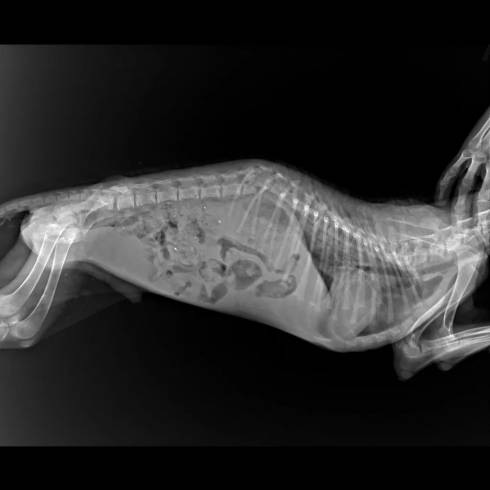

В Караганде дети записали трогательное видео с просьбой спасти собаку с переломом позвоночника

В Караганде дети спасли от страшной гибели собаку, которую, очевидно, сбила машина. Пес получил перелом позвоночника и не мог самостоятельно двигаться. Дети очень переживали за пса. О несчастье с собакой узнали их родители, и так пес оказался в руках ветеринаров. Они надеются, что после лечения он снова сможет бегать.